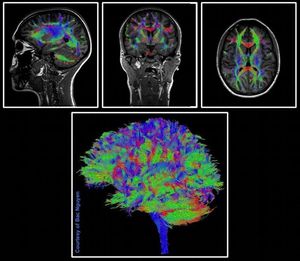

Simultaneous Multi-Slice (SMS) speeds up imaging significantly through the simultaneous excitation and readout of multiple slices. Simultaneous Multi-Slice Diffusion bring advanced neuro applications into clinical routine – offering various advantages. For diffusion-weighted imaging, slice acceleration can be used to reduce scan time and/or achieve higher spatial/diffusion resolution. Diffusion Tensor Imaging (DTI) obtained with 1.5mm isotropic voxel size, b0 and b1000, 64 directions, within approximately 6min. GRAPPA 2 and Slice Acceleration 2 were used. Siemens Prisma 3 Tesla. Images courtesy of Bac Nguyen. #MRI #SMS #DWI #diffusion